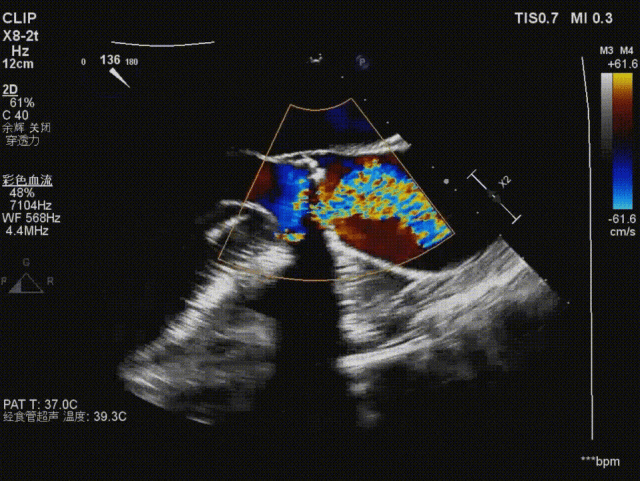

瓣膜释放后造影及食道超声评估可见瓣膜释放形态欠佳,可见瓣周漏,并发现右冠开口血流缓慢,高度警惕右冠灌注障碍;

瓣膜释放后造影

在保护右冠的前提下,精确释放开窗支架,恢复右冠灌注,随后行球囊后扩确保瓣膜贴壁充分,兼顾瓣膜功能与冠脉通畅;

右冠保护下球囊后扩

复查造影及食道超声示瓣膜位置,形态满意,瓣周漏较前明显好转,右冠血流恢复,无栓塞迹象;